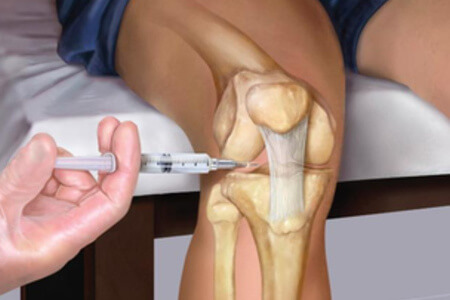

Кроме состава и питания самого хряща на его состоянии отражается и синовиальная жидкость. В этом случае речь идет о применении гиалуроновой кислоты. Это новая методика лечения, получившая название жидкий протез. Вводятся препараты в сустав только в виде инъекций. Попадая в суставную полость, гиалуроновая кислота, идентичная натуральной, восстанавливает вязкость жидкости и буквально обволакивает хрящ, предотвращая дальнейшее трение. При этом значительно улучшается питание, и регенерация происходит естественным путем.